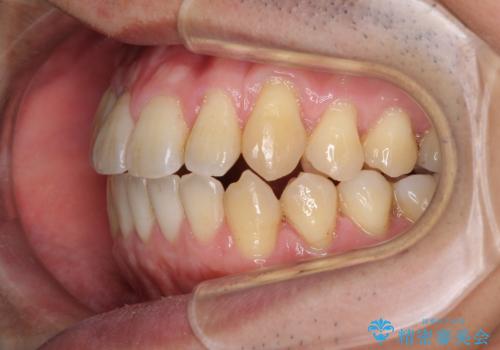

インビザラインによる反対咬合の改善は、上の歯が下の歯を乗り越えていく期間に咬み合わせが非常に不安定となり、治療が長期化することがあります。

また、ワイヤー矯正と異なり歯軸改善の強い力を前歯にかけるため、反対咬合で裏側にある歯の歯肉が退縮しやすくなります。

矯正治療により元々気になっていた八重歯と、反対咬合が改善された歯の2本に対して根面被覆を行い、審美面の改善も達成しました。